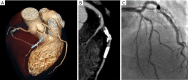

Figure 2

Case of false positive displaying intrastent restenosis at cardiac computed tomography (CCT). (A) Volume rendering; (B) multiplanar reconstruction of the left anterior descending coronary artery; (C) corresponding conventional angiogram depicting intrastent patency.